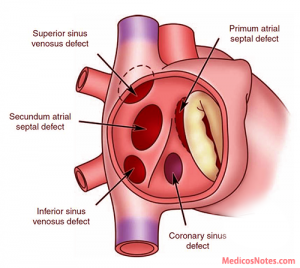

心房中隔欠損症は数種類のタイプに分けられます。最も多く遭遇する二次孔欠損型心房中隔欠損症が8-9割を占め、欠損孔サイズや辺縁の形態によりAmplatzerなどの閉鎖栓によるカテーテル閉鎖が行われることは周知と思います。一方、静脈洞型(sinus venosus type)心房中隔欠損症は心房中隔欠損症の5-10%程度を占め、その他の欠損タイプと同様に、現在のところ開胸手術が唯一の確立された治療法になります(図1)。